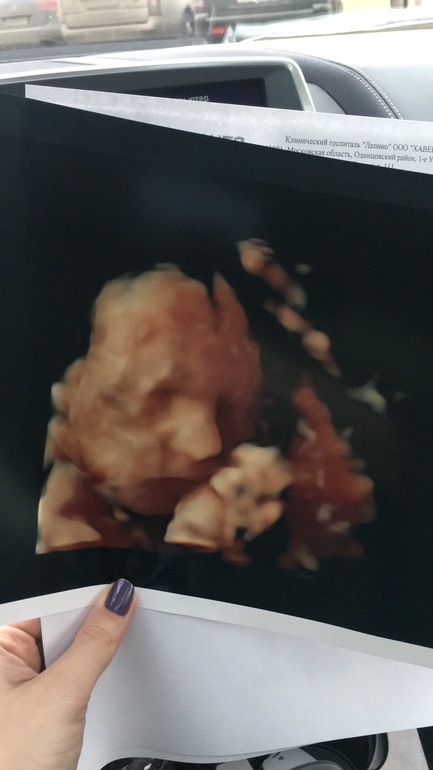

На УЗИ вчера пошла к Мальмберг О.Л...да она профессиональна, но мне не понравилось что со мной огрызнулись и огромной силой давили на живот чтобы развернуть личико ребенка для фото) за 12к за узи...прям печально. Но патологий нет

Фото прекрасное! Щеки наел мой мальчик, но было жутко неприятно...но ради фото терпела) вагинально уже не смотрела

Головой лежим вниз, 500гр весим! И фото цветное! Нос огроменный)